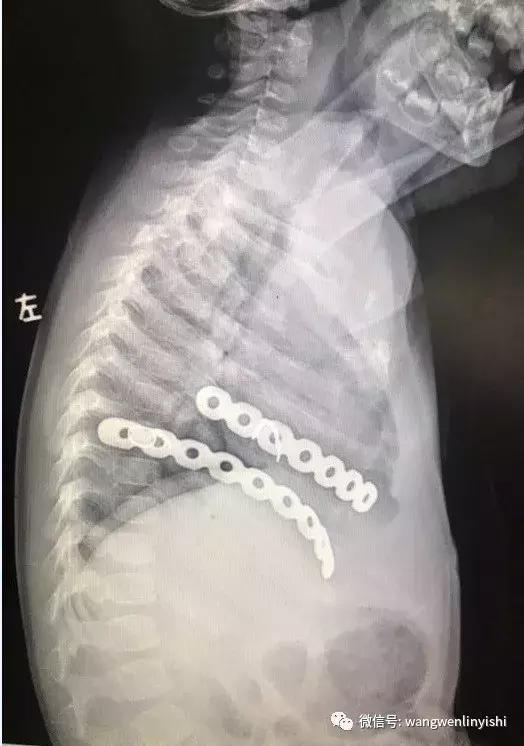

术前查体,前胸壁与右侧胸壁有陈旧性手术疤痕,疤痕愈合良好。右侧肩胛下角内侧可见3X3CM大小囊性包块,包块大小可以随体位变化改变。X线提示右侧胸壁内两条肋骨固定钢板。手术在全麻下完成。左侧卧位,先经右侧胸壁疤痕处做皮肤切口,先显露钢板,将其取出,然后于囊肿表面做皮肤切口,向深部游离囊肿。术中发现囊肿位于肩胛下角内侧,大小约3X3X6CM。将囊肿完整切除后,打开囊肿,见其中为淡黄色液体,无特殊组织增生。手术操作顺利,历时30分钟完成,未发生并发症。

图3,第一次手术后的塑形板。